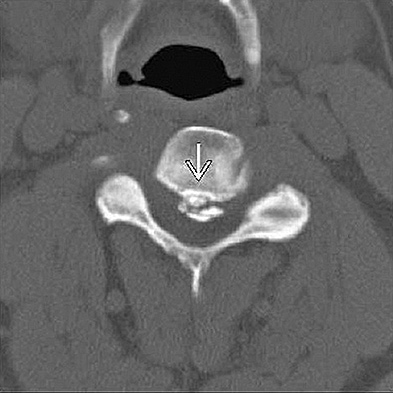

CLINICAL SITUATION

Figure 1 shows a CT from the cervical spine of an 85-year-old woman who fell from a standing height 1 week earlier. She is independent and ambulatory and resides in an assisted living facility. She reports persistent neck pain but denies arm pain or weakness. She is neurologically intact.

Fractures in this region of C2 have a high risk of

Discussion: C

Increased displacement and angulation of odontoid fractures have an increased risk of nonunion. Surgical stabilization has reduced the risks of mortality without increasing the risk of complications compared with nonsurgical treatment options. When treating odontoid fractures, halo vest

immobilization has been shown to increase the risk of dysphagia in the elderly.

Question 7 of 100

4. posterior C1-2 arthrodesisDiscussion: D

Increased displacement and angulation of odontoid fractures have an increased risk of nonunion. Surgical stabilization has reduced the risks of mortality without increasing the risk of complications compared with nonsurgical treatment options. When treating odontoid fractures, halo vest immobilization has been shown to increase the risk of dysphagia in the elderly.

What are the risks associated with halo vest treatment, compared with hard-collar treatment?

4. Dysphonia Discussion: B

Increased displacement and angulation of odontoid fractures have an increased risk of nonunion. Surgical stabilization has reduced the risks of mortality without increasing the risk of complications compared with nonsurgical treatment